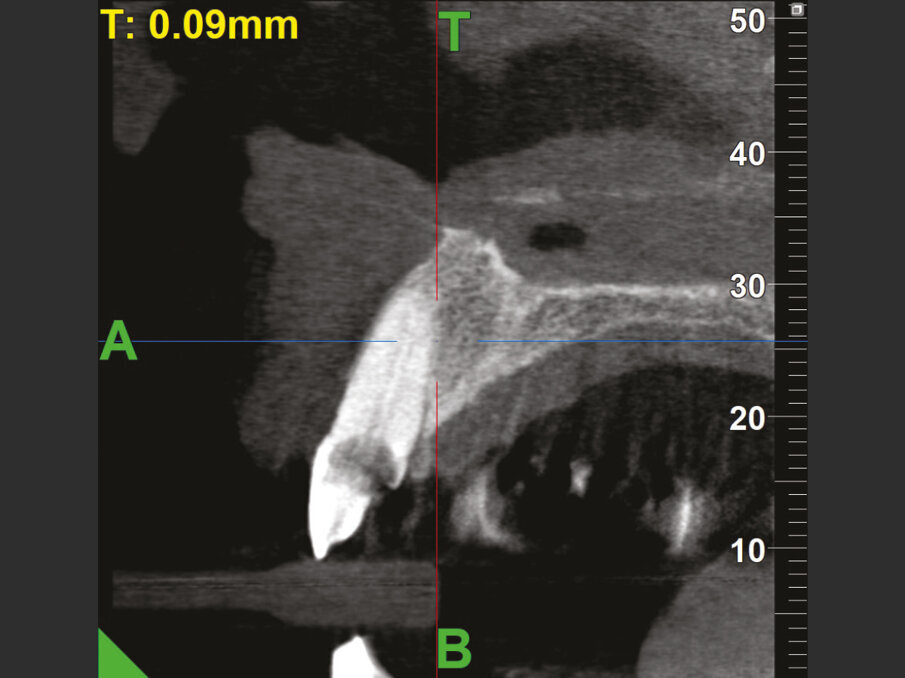

Data la profondità della lesione, le opzioni terapeutiche che consentono il mantenimento dell’elemento devono prevedere necessariamente il ripristino dell’ampiezza biologica tramite chirurgia ossea resettiva o trazionamento rapido dell’elemento. La prima ipotesi viene scartata per l’inevitabile slivellamento delle parabole e perdita delle papille interdentali che ne sarebbero derivate; la seconda per il rifiuto della paziente di sottoporsi al trattamento ortodontico, pur se per un periodo di tempo limitato. Si procede quindi con un’indagine radiografica tridimensionale con tecnica Cone Beam (MYRAY Hyperion X9 Pro), per valutare la possibilità di sostituire l’elemento con una corona a supporto implantare. I tagli in sezione sagittale (Fig. 2b) mostrano la presenza di una corticale ossea vestibolare integra e la presenza di una quantità di osso apico-palatale sufficiente per poter ottenere una buona stabilità implantare (classe I secondo la classificazione di Cardaropoli9).

Fig. 2b - CBCT iniziale con MyRay Hyperion X9 Pro.